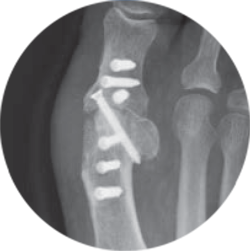

Ya que las placas son invisibles para los rayos X al contar con sulfato de bario para baja visibilidad, ofrecen una experiencia de diagnóstico por imágenes radiotransparente y libre de artefactos.